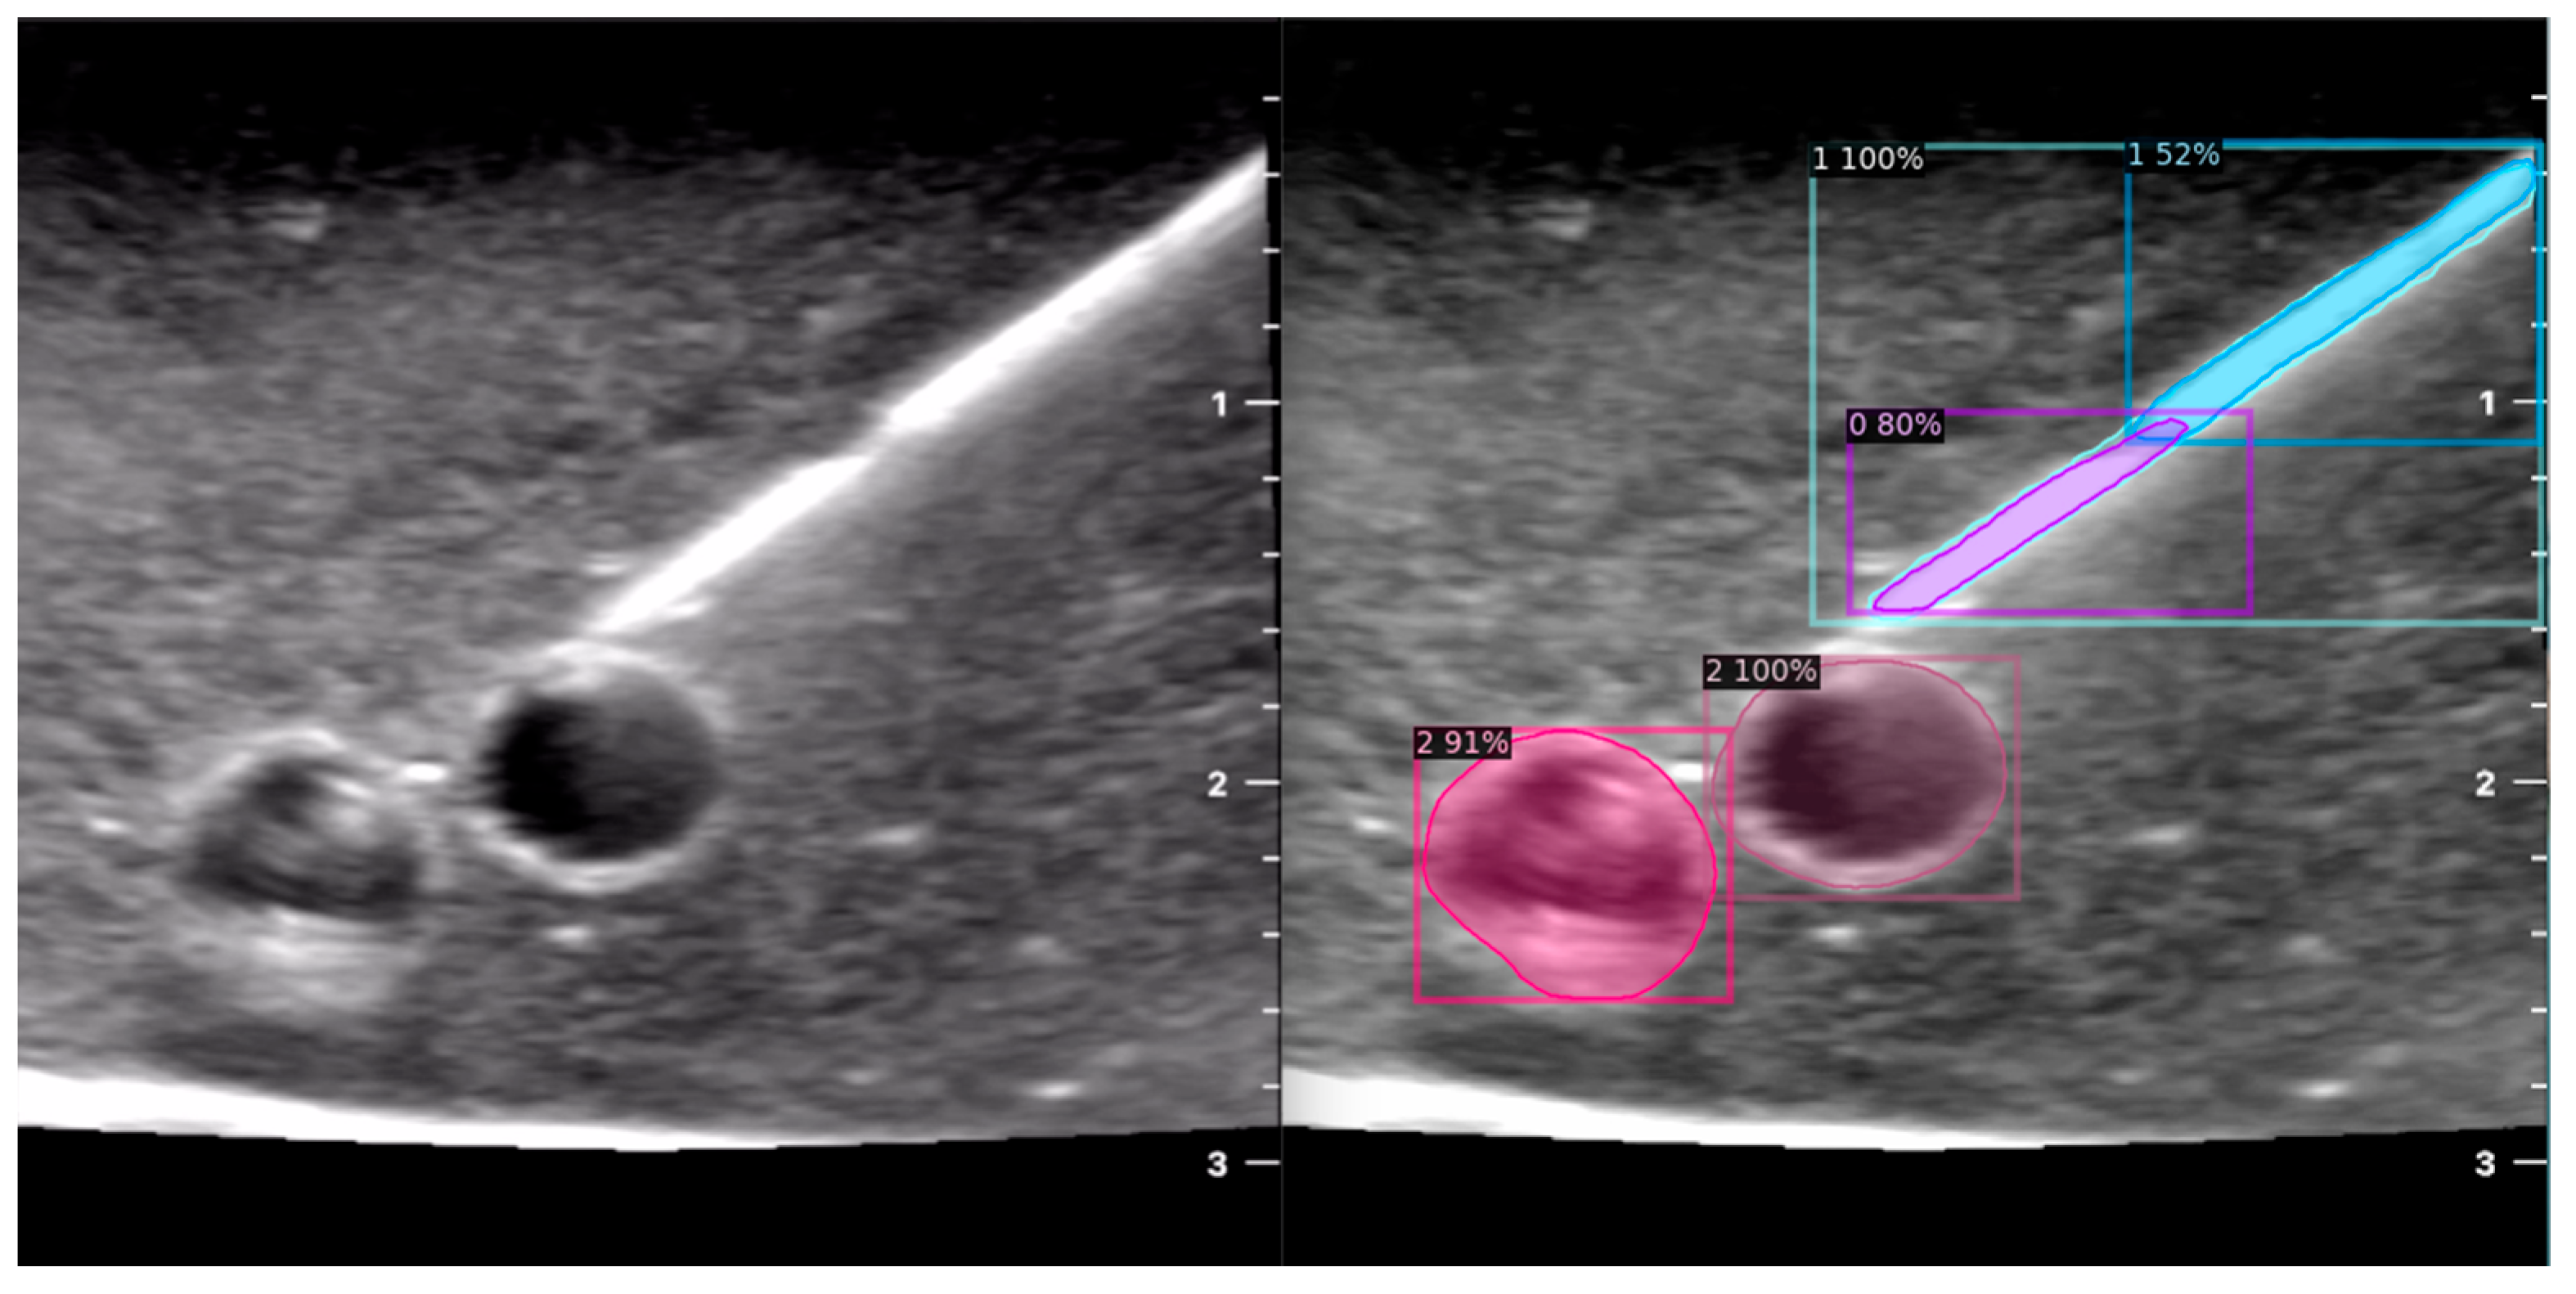

When the model is applied, the original ultrasound image is overlaid with a new layer that presents the detection results, offering insights into predicted target areas (Figure 4 and Figure 5).

The segmentation area represents the region identified by the model as each object class (needle tip, needle body, blood vessel, or nerve bundle). This area is visually highlighted, allowing for a clear understanding of what structure is of interest. To provide additional context, a bounding box in the shape of a square is placed around the segmentation area, enclosing the detected object and providing a concise representation of its location. These are illustrated in Figure 4, Figure 5 and Figure 6, with original images on the left and overlayed images on the right for our three different phantom models.

To facilitate easy differentiation between different objects, Detectron2 generates a detection name based on the metadata of the COCO file. This name provides information about the specific object type, enabling the effective categorisation and analysis of different structures.

In order to assess the confidence level of the model’s predictions, a confidence percentage is assigned for each object class labelled (Figure 4, Figure 5 and Figure 6). This percentage represents the probability of a true positive detection by the model. It quantifies the model’s level of certainty regarding the accuracy of its prediction for each detected defect.

Figure 4. Model inference in Phantom A (Agar 2.5% with septanol and psyllium husk).